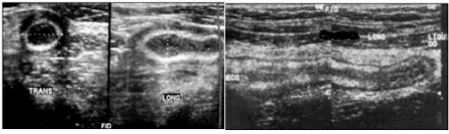

Imagem ultrassonográfica de paciente do sexo masculino, 30 anos de idade, com quadro de dor abdominal difusa, hemograma com leucocitose e radiografia abdominal simples com achados inespecíficos.

Com base nos dados apresentados, assinale a alternativa com a melhor hipótese diagnóstica.